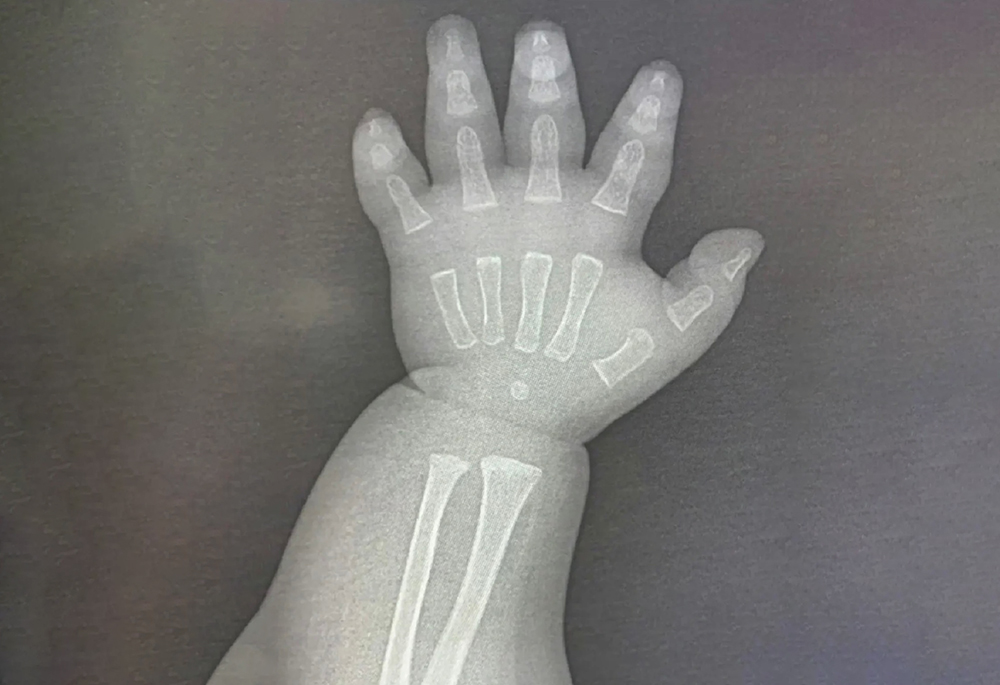

在出生時新生兒的骨骼處於不太成熟的階段,主要表現為骨組織低度礦化以及骨骼稚嫩。然而影響骨骼成熟度的發展因素有很多,比如:遺傳、營養、環境、生長激素以及活動程度等。一般來說在新生兒的第三個月時,其骨骼已經得到了發育,這一階段主要表現為骨量增加、礦物質含量提高、骨骼穩定性增強等等。要知道骨齡成熟速度通常為每年1歲,大致與生活年齡相當。但是骨骼的發育受到先天遺傳因素以及後天營養、運動、睡眠、心理等多種因素的影響,骨齡的成熟速度往往與年齡增長並不相符。由於不合理的餵養及生活習慣,往往會加快骨齡的成熟速度,導致骨齡超前,大於實際年齡。接下來我們來具體說下寶寶在骨骼發育期,家長經常踩的三個雷區。

剛開始學走路的寶寶搖搖晃晃,長輩們擔心寶寶摔倒所以習慣性的牽著寶寶的手走路,千萬別這麼做,嬰幼兒骨骼硬度差、彈性大。尤其兩歲以下孩子剛學會走路,家長長時間單側向上牽領走,孩子重心易發生偏移,這對骨骼發育不利如若寶寶不小心跌到,會有脫臼的可能